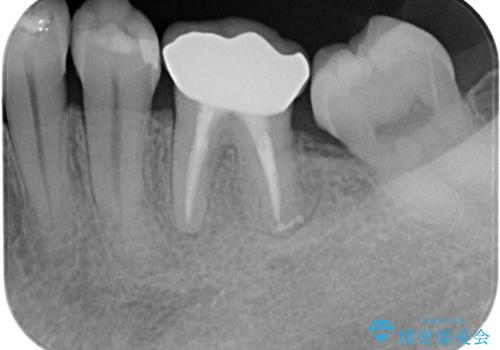

下顎大臼歯の再根管治療とオールセラミッククラウンによる補綴治療

根管治療後は、ファイバーコアによる土台と、オールセラミッククラウンによる補綴治療を行いました。

なお、最後方臼歯が手前に傾いていることで汚れがたまりやすい形態を改善するための矯正治療も提案しましたが、希望されなかったためそのまま補綴治療を行っています。

根管治療後、噛んだ時の違和感は消失しました。